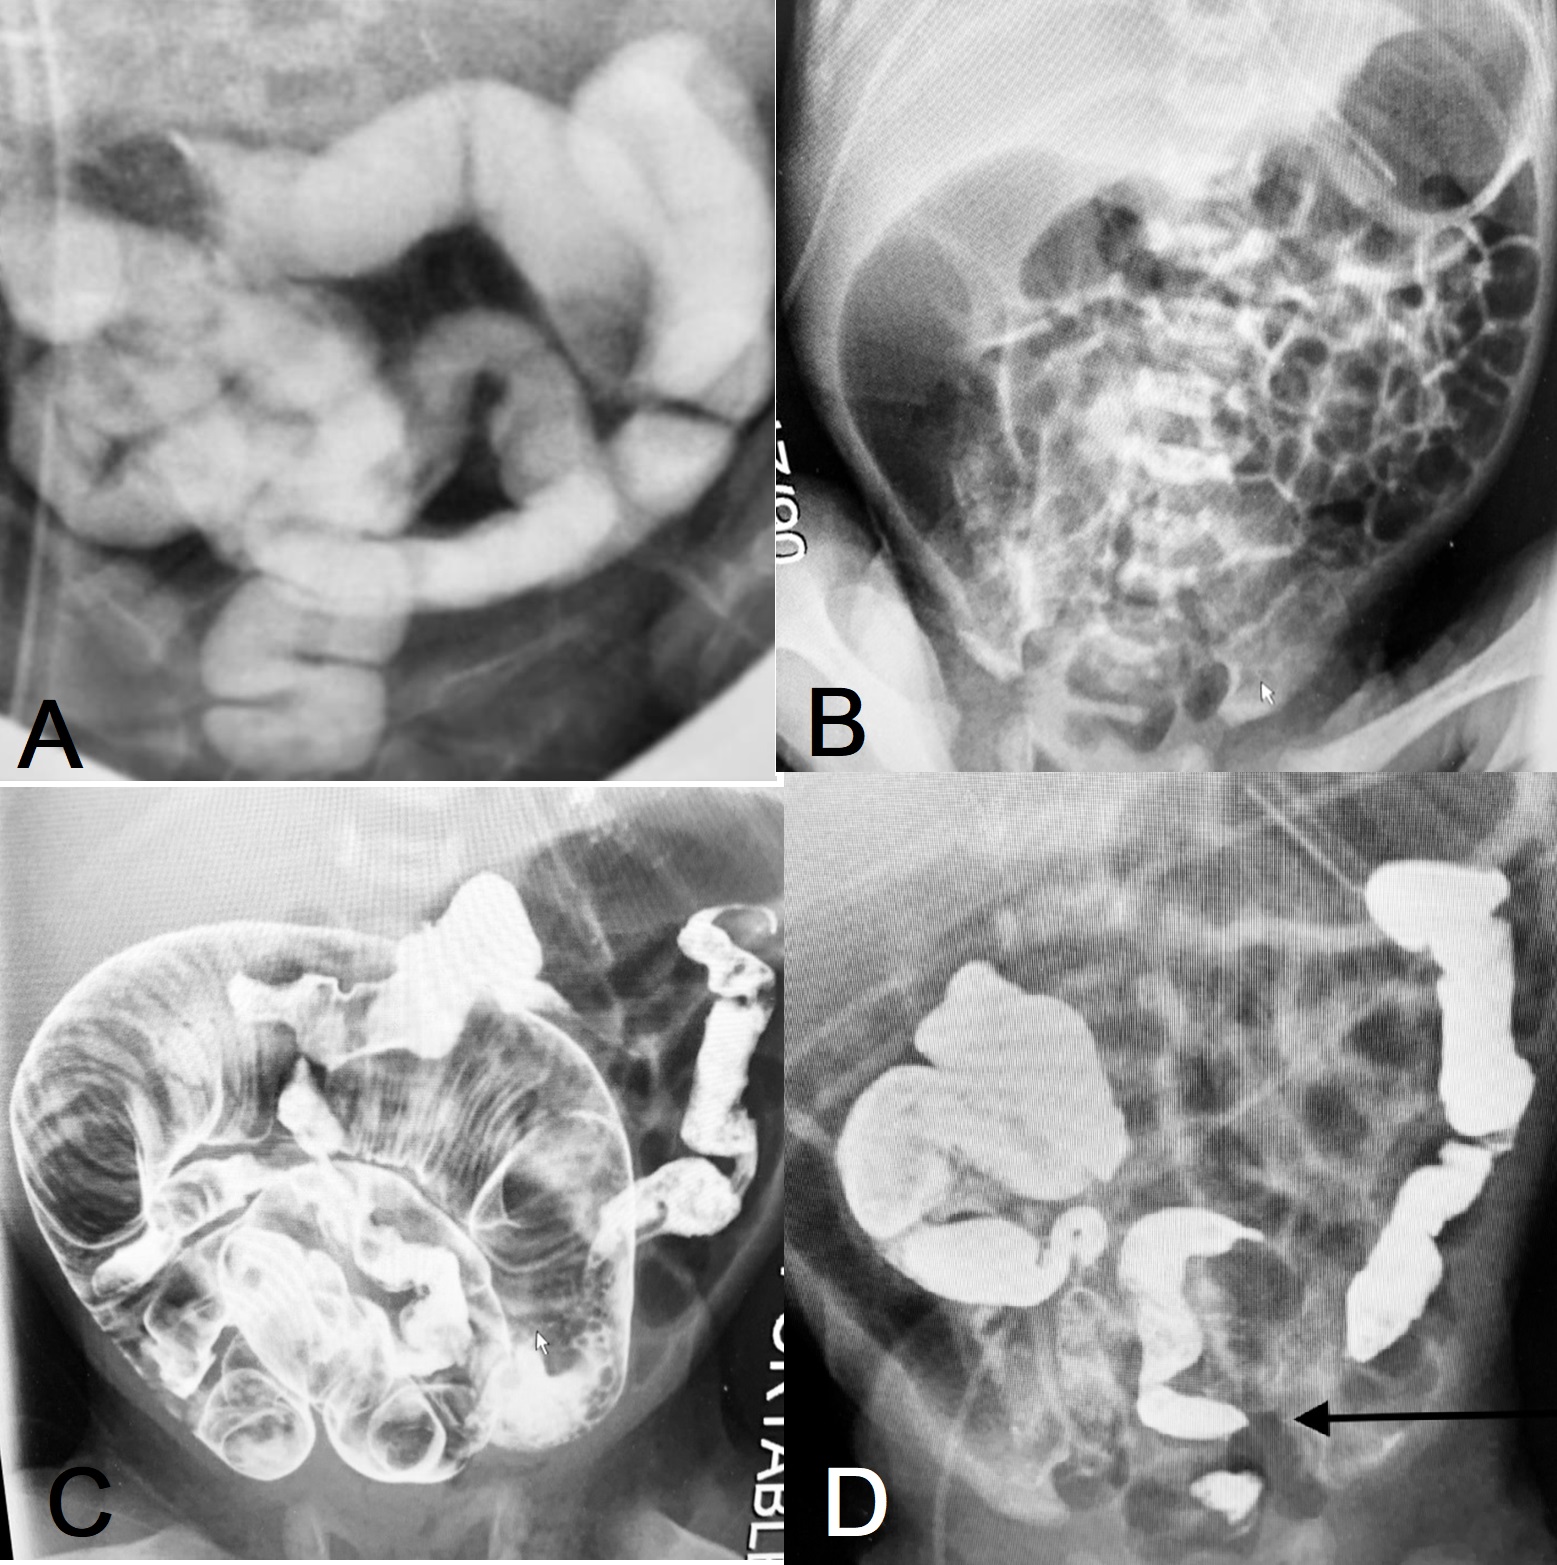

A 29-week GA 1.2 Kg boy was delivered by Cesarean section, because of breech presentation. His mother was 39 years old, G4P1. Passage of meconium was delayed, and a contrast enema was obtained. Multiple meconium plugs were loosened, and the baby had a sizable evacuation (Fig. 1A). Feedings were begun but not tolerated; and after a week’s discouragement, an abdominal radiograph was obtained that showed intestine of varying caliber, the hallmark of mechanical intestinal obstruction (Fig. 1B). An Upper GI small bowel follow-through showed slow, but the eventual passage of contrast through the dilated, partially obstructed small bowel, through diminutive terminal ileum, eventually reaching the colon and rectum (Fig. 1C,1D). We decided to withhold feedings for 7-10 days and instill Mucomyst (N acetylcysteine). This strategy was successful, and the infant was spared an ileostomy and is now tolerating full feedings. The baby’s Cystic Fibrosis screen (IRT) was normal.

Figure 1: A) Contrast outlines the colon. B) X-ray abdomen showing dilated small bowel loops. C) Contrast outlines the dilated small bowel loops. D) ultimately the contrast evacuates to the rectum (Arrow).